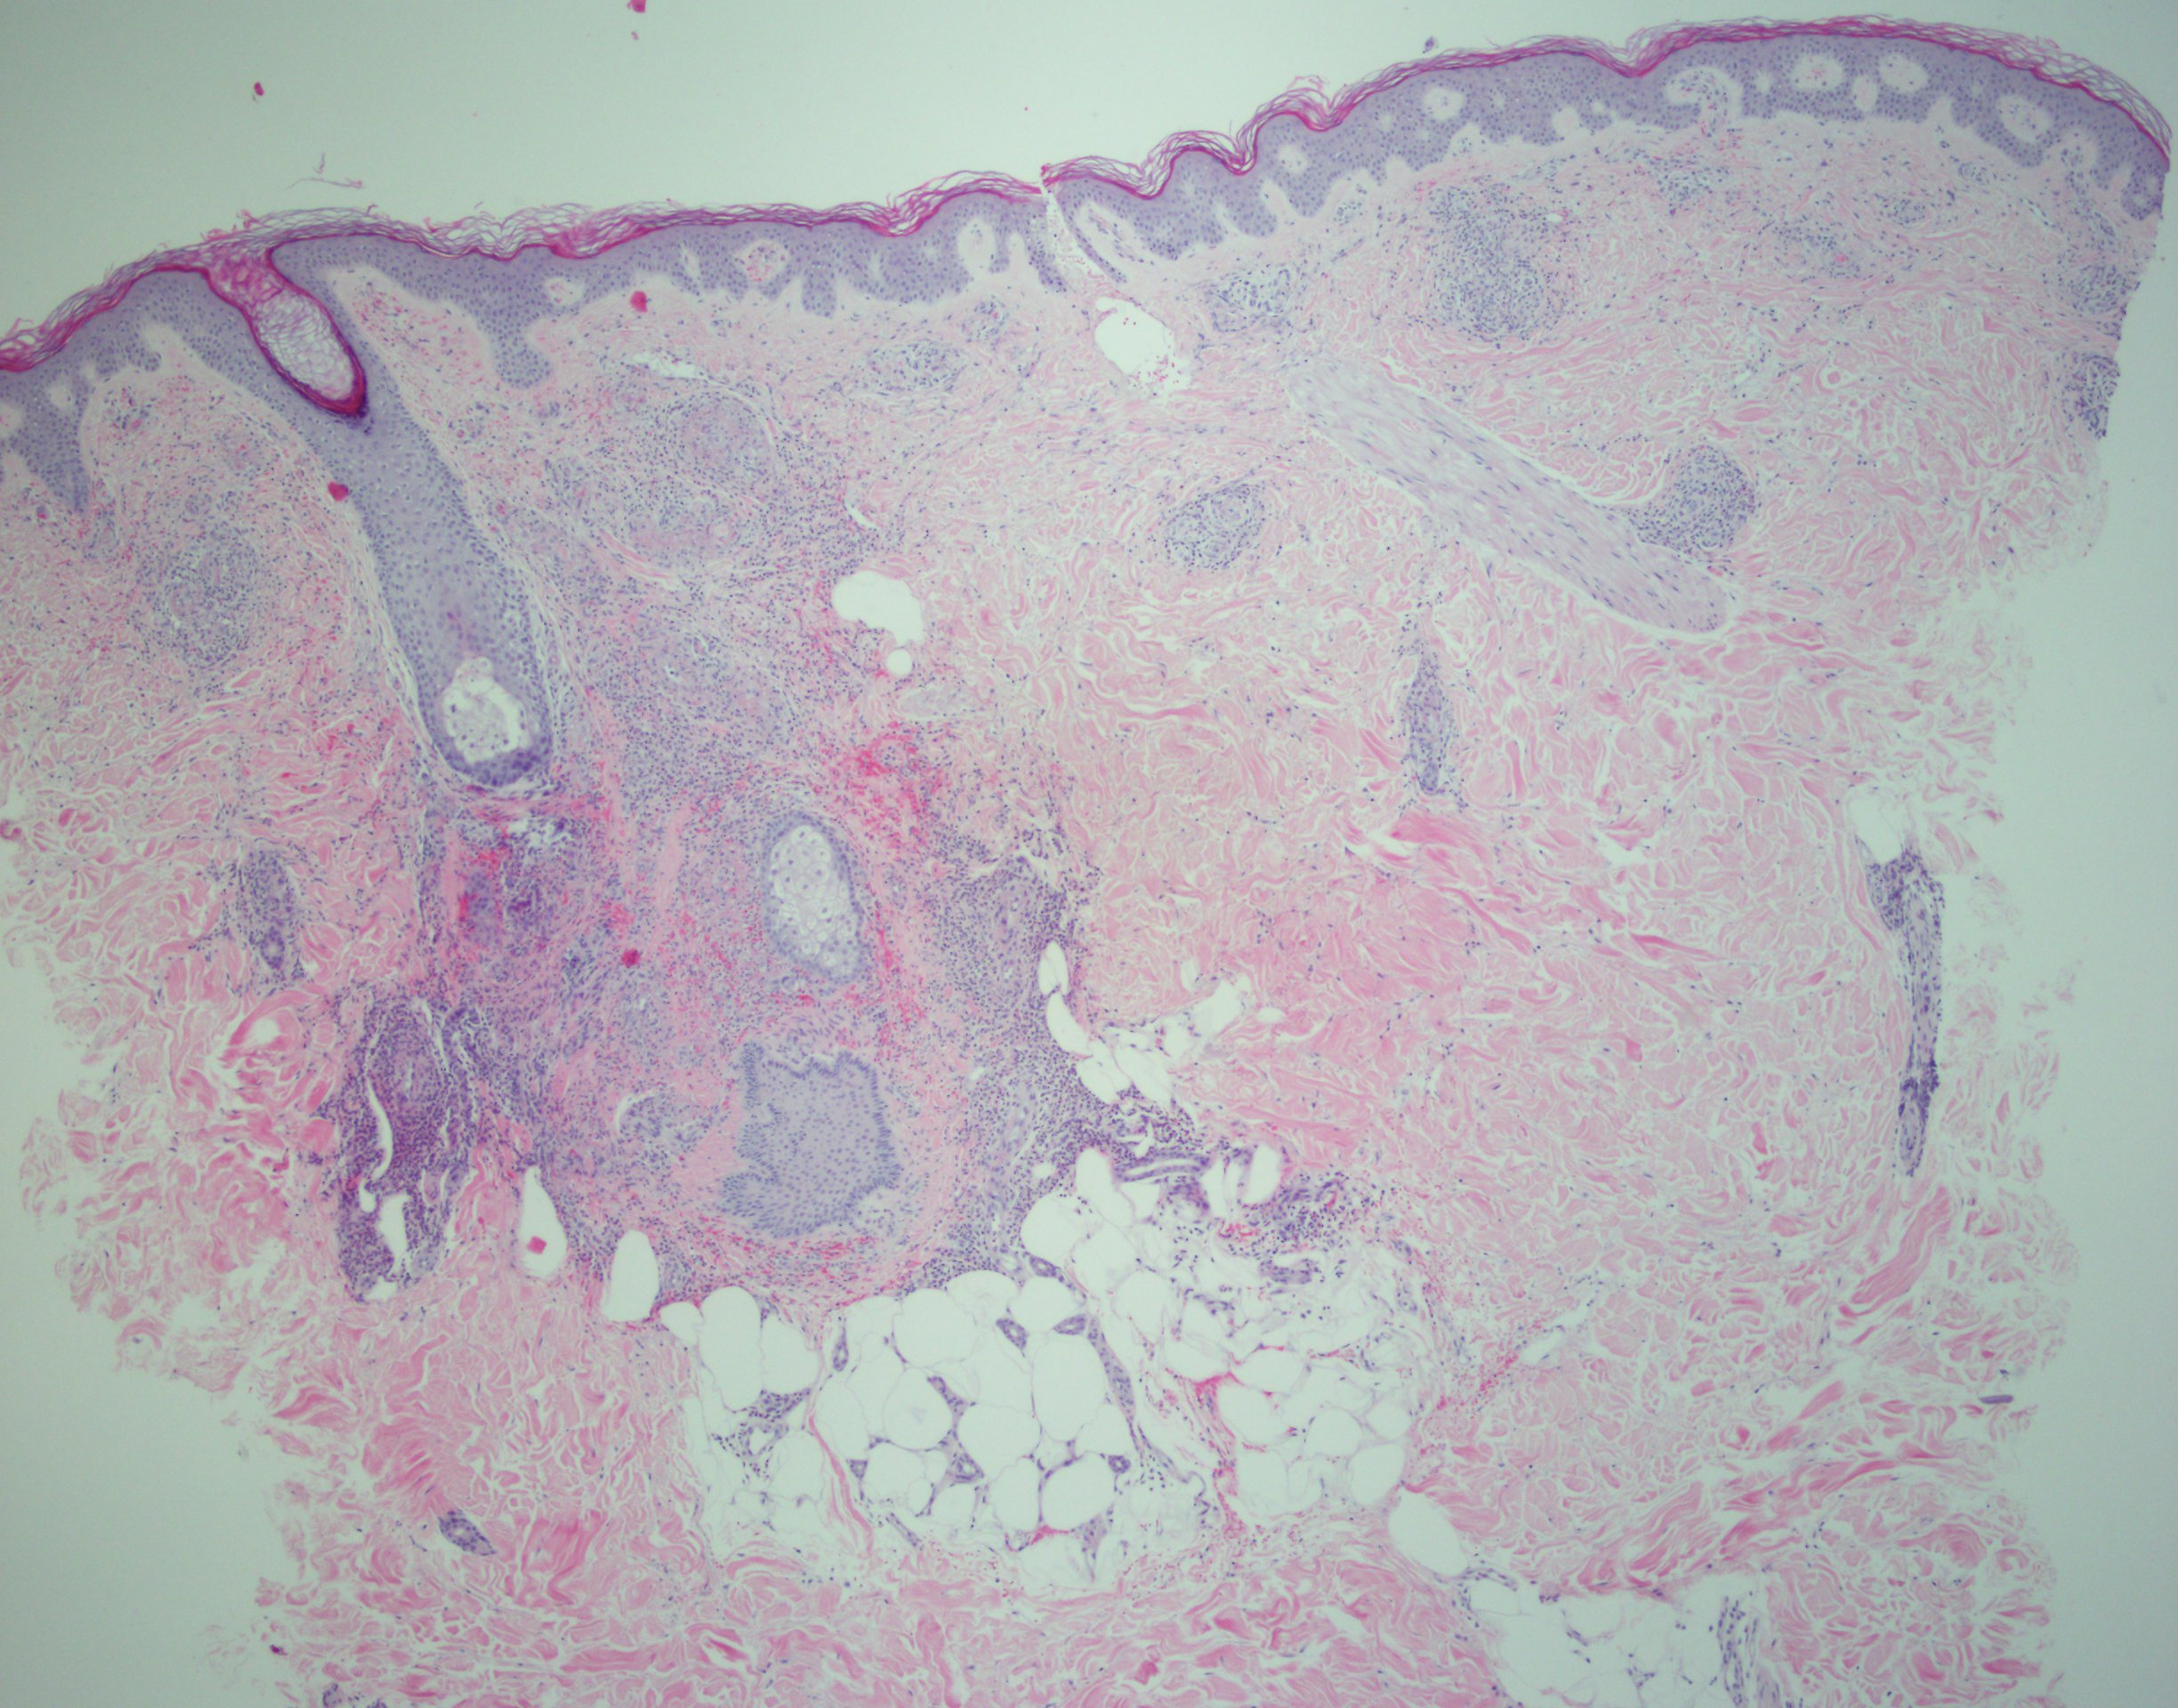

The rapid development of coalescing palpable purpura, acute kidney injury, and joint arthralgias subsequent to initiating a new medication strongly suggests a hypersensitivity vasculitis.1 Histopathologic study revealed neutrophilic vasculitis with red blood cell extravasation, perivascular and interstitial neutrophils, nuclear dust, and vascular damage with fibrin deposition (Figures 2-4). Under direct immunofluorescence, deposition of immunoglobulin G, immunoglobulin A, C3, immunoglobulin M, and fibrin were observed in the blood vessels and vessel walls. These findings confirmed the diagnosis of LCV.2

Figure 2. Section from a punch biopsy of skin lesions demonstrating neutrophilic vasculitis with erythrocyte extravasation, perivascular and interstitial neutrophils, nuclear dust, and vascular damage with fibrin deposition (hematoxylin-eosin; ×40 magnification).